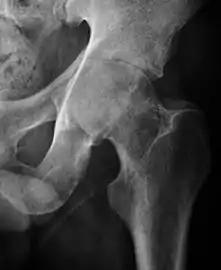

Plain radiography allows us to categorize the hip as normal or dysplastic or with impingement signs (pincer, cam, or a combination of both). Besides these, pathologic processes like osteoarthritis, inflammatory diseases, infection, or tumors can also be identified (Figure 1).[1]

Figure 1.

In adults, one of the main indications for radiographs is the detection of osteoarthritic changes (Figure 1(e)). Nevertheless, radiographs usually detect advanced osteoarthritis that can be graded according to the Tönnis classifications. The grading system ranges from 0 to 3, where 0 shows no sign of osteoarthritis. Intermediate grade 1 shows mild sclerosis of the head and acetabulum, slight joint space narrowing, and marginal osteophyte lipping. Grade 2 presents with small cysts in the femoral head or acetabulum, moderate joint space narrowing, and moderate loss of sphericity of the femoral head. Grade 3 is the severest form of osteoarthritis, which manifests as severe narrowing of the joint space, large subchondral cyst with productive bone changes that may lead to deformity of the bone components of the joint, while secondary osteoarthritis due to calcium pyrophosphate deposition can be diagnosed when calcification of hyaline cartilage and fibrocartilage is detected.[1]

There are other pathological conditions that can affect the hip joint and radiographs help to make the appropriate diagnosis. Acute bacterial septic arthritis can be diagnosed by radiographs when a fast regional osteoporosis and destructive monoarticular process develops (Figure 1(f)). In case of tuberculous or brucella arthritis it is manifested as a slow progressive process, and diagnosis may be delayed.[1]